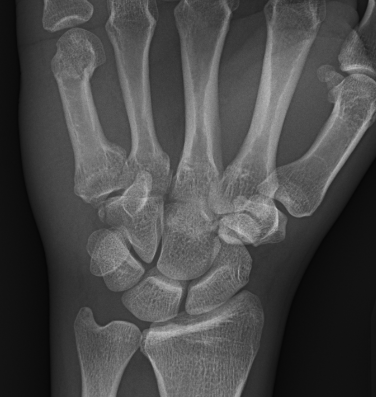

What’s the diagnosis? Gepost op 12 maart 2019 door netwerkvsseh What’s the diagnosis? @emdaily.cooperhealth.org Dit delen: Delen op X (Opent in een nieuw venster) X Share op Facebook (Opent in een nieuw venster) Facebook Delen op LinkedIn (Opent in een nieuw venster) LinkedIn E-mail een link naar een vriend (Opent in een nieuw venster) E-mail Afdrukken (Opent in een nieuw venster) Print Vind-ik-leuk Aan het laden... Gerelateerd